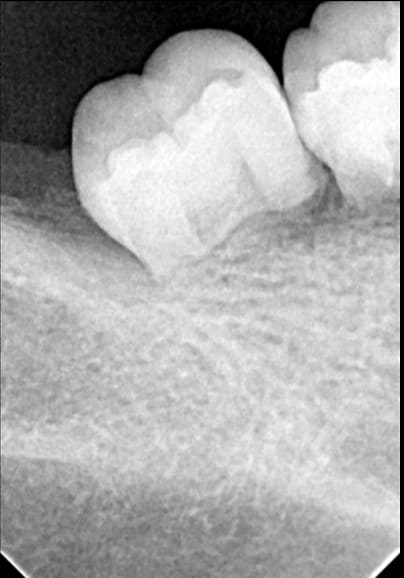

Avez vous déjà rencontré ce type de "pathologie". Le patient a 28 ans, n'a pas de problème de santé, n'a pas eu d'ortho et présente une béance antérieure (il y a aussi des problèmes d'édification radiculaire sur les antérieures) , j'élimine donc la cause occlusale.

A oui impressionnant, ton cas semble bien être des résorptions, moi c'est plutôt une un problème d'édification car on a bien des apex arrondis. De toute façon, c'est sûr qu'il n'y a pas grand chose à faire...